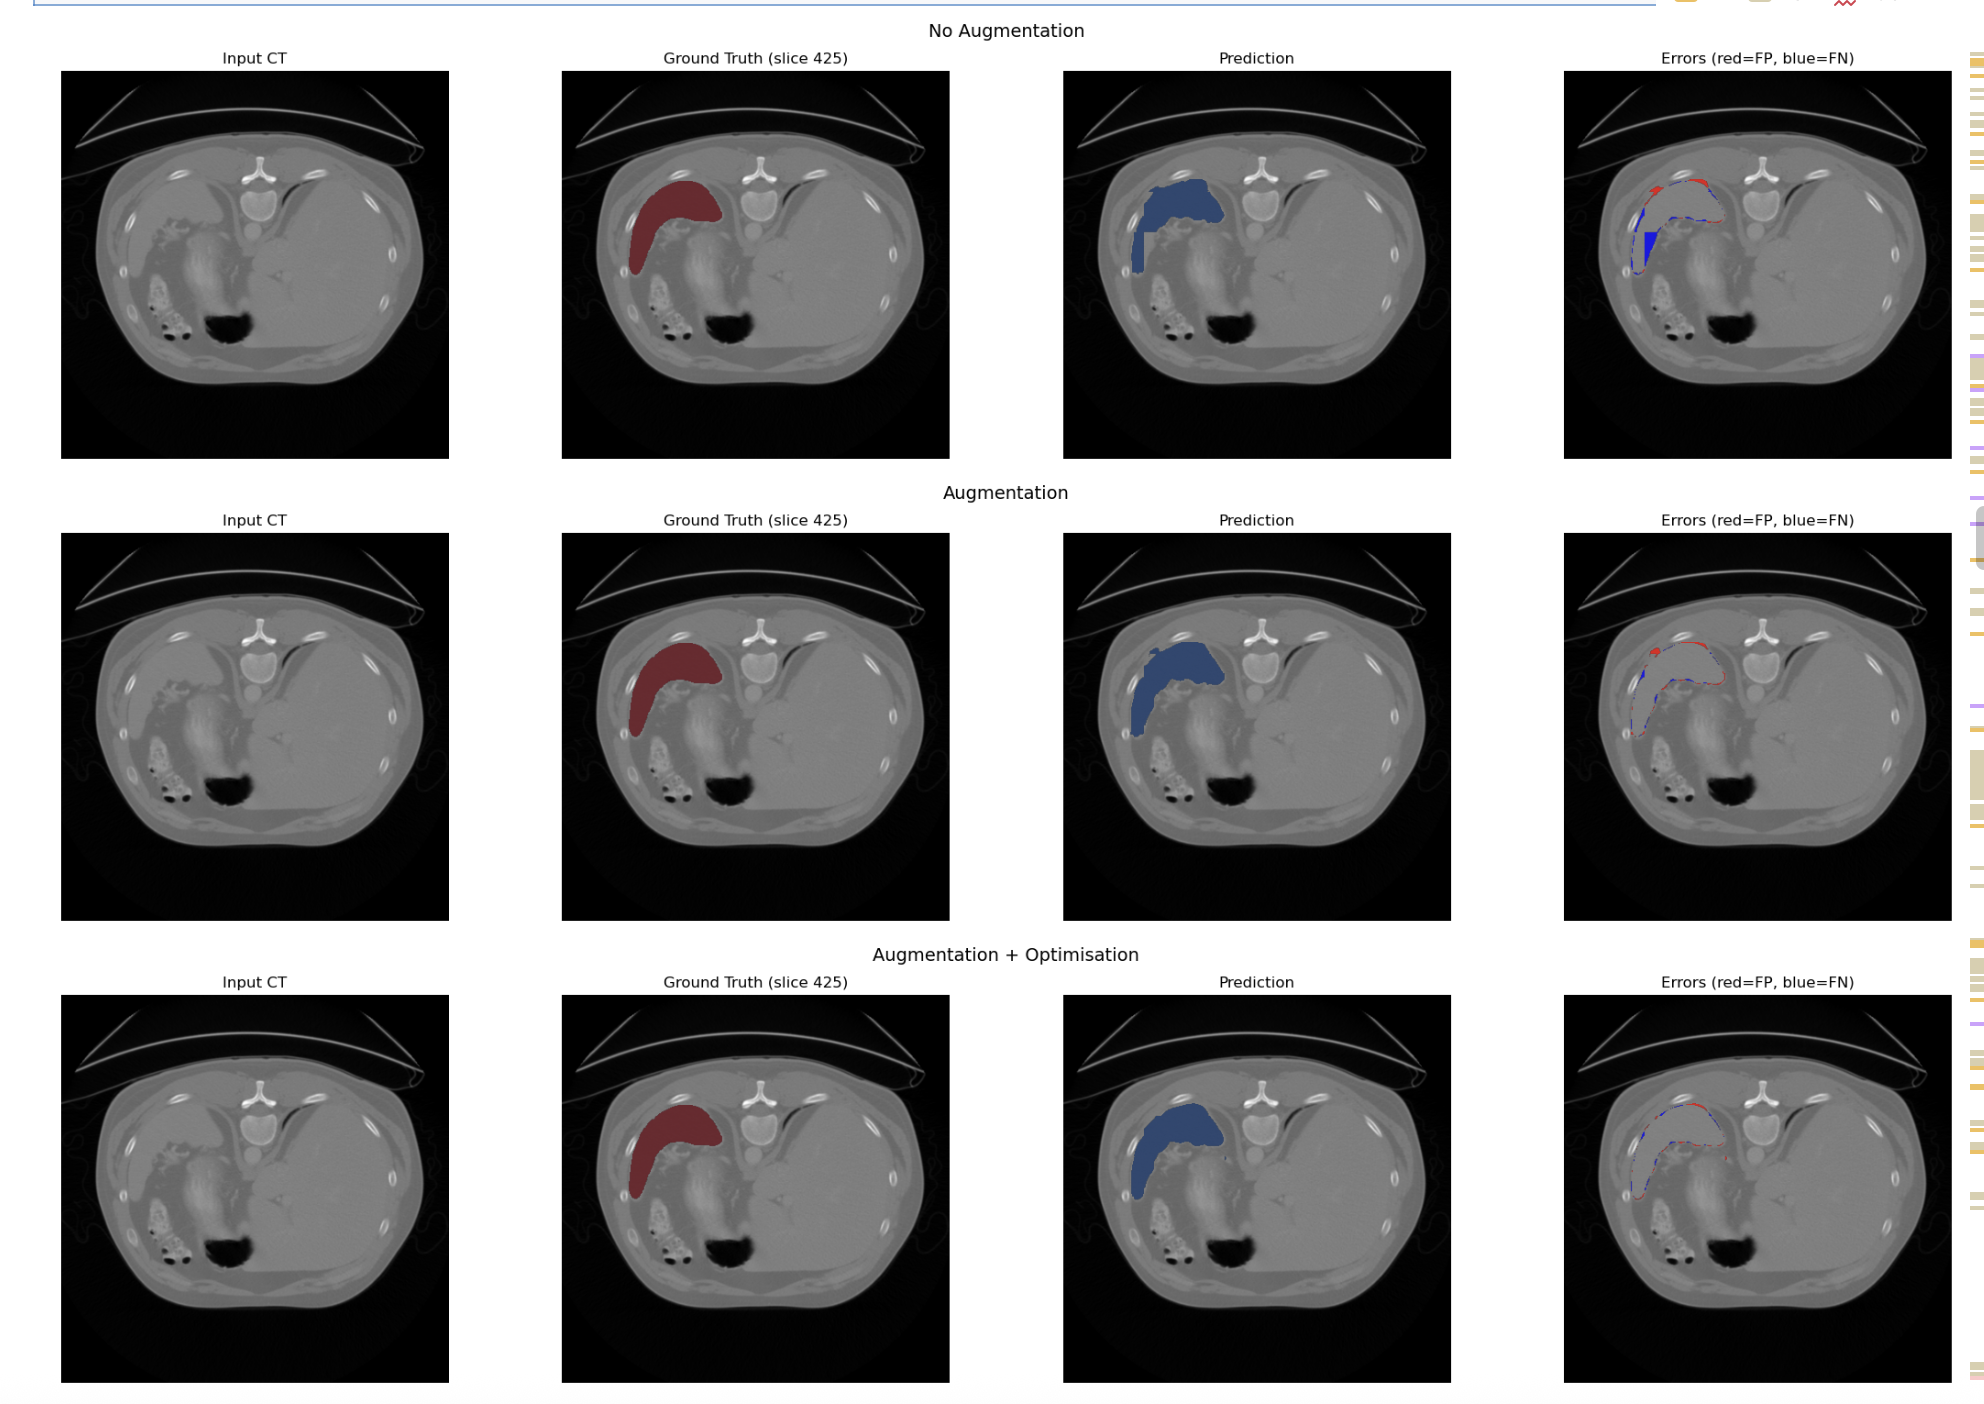

Model A,B and C

- Baseline U-Net: Standard 3D U-Net without attention gating.

- Attention U-Net: Integrated Attention Gates to suppress background anatomy.

- Attention U-Net with Data Augmentation: Random Affine and Elastic Deformation of data introduced to mimic normal anatomical variation/scanner artifacts

- Attention U-Net with Data Augmentation and Optimisation: Implemented AdamW optimiser and Cosine Annealing Scheduler